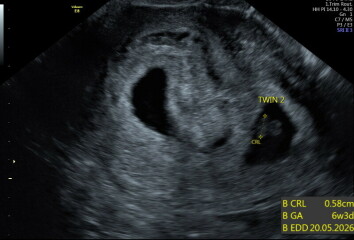

I thought I was 6w 5d going in - Twin A measures 6w 6d and Twin B measures 6w 3d. Both have heartbeats! They're in two sacs, so likely DCDA twins.

Scan pics attached 😀